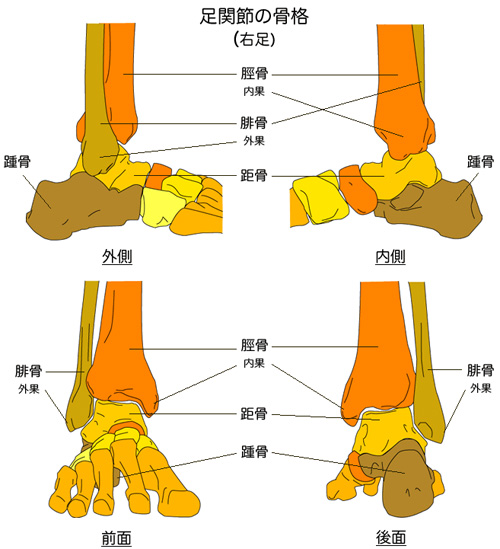

足関節の解剖について

代表的な靭帯損傷の部位

1.前距腓靱帯:ATFL(anterior talofibular ligament)

距骨の前方への動きを抑えて、底屈時まで緊張し内反を規制する。

足関節靱帯損傷で損傷される頻度が最も多い。

2.踵腓靱帯:CFL(calcane-ofibular ligament)

足関節0°での内転のとき緊張し、底屈時には弛緩する。前距腓靱帯と合併して損傷が多く、内返しストレスX線での距骨傾斜角:TTA(talar tilt angle)が大きくなる。

3.後距腓靱帯:PTFL(posterior talofibular ligament)

外側靱帯の中で最も強靭な靱帯で、底屈時に弛緩する。

過度の背屈によりまたは、ATFL・PTFLの断裂後に損傷する。